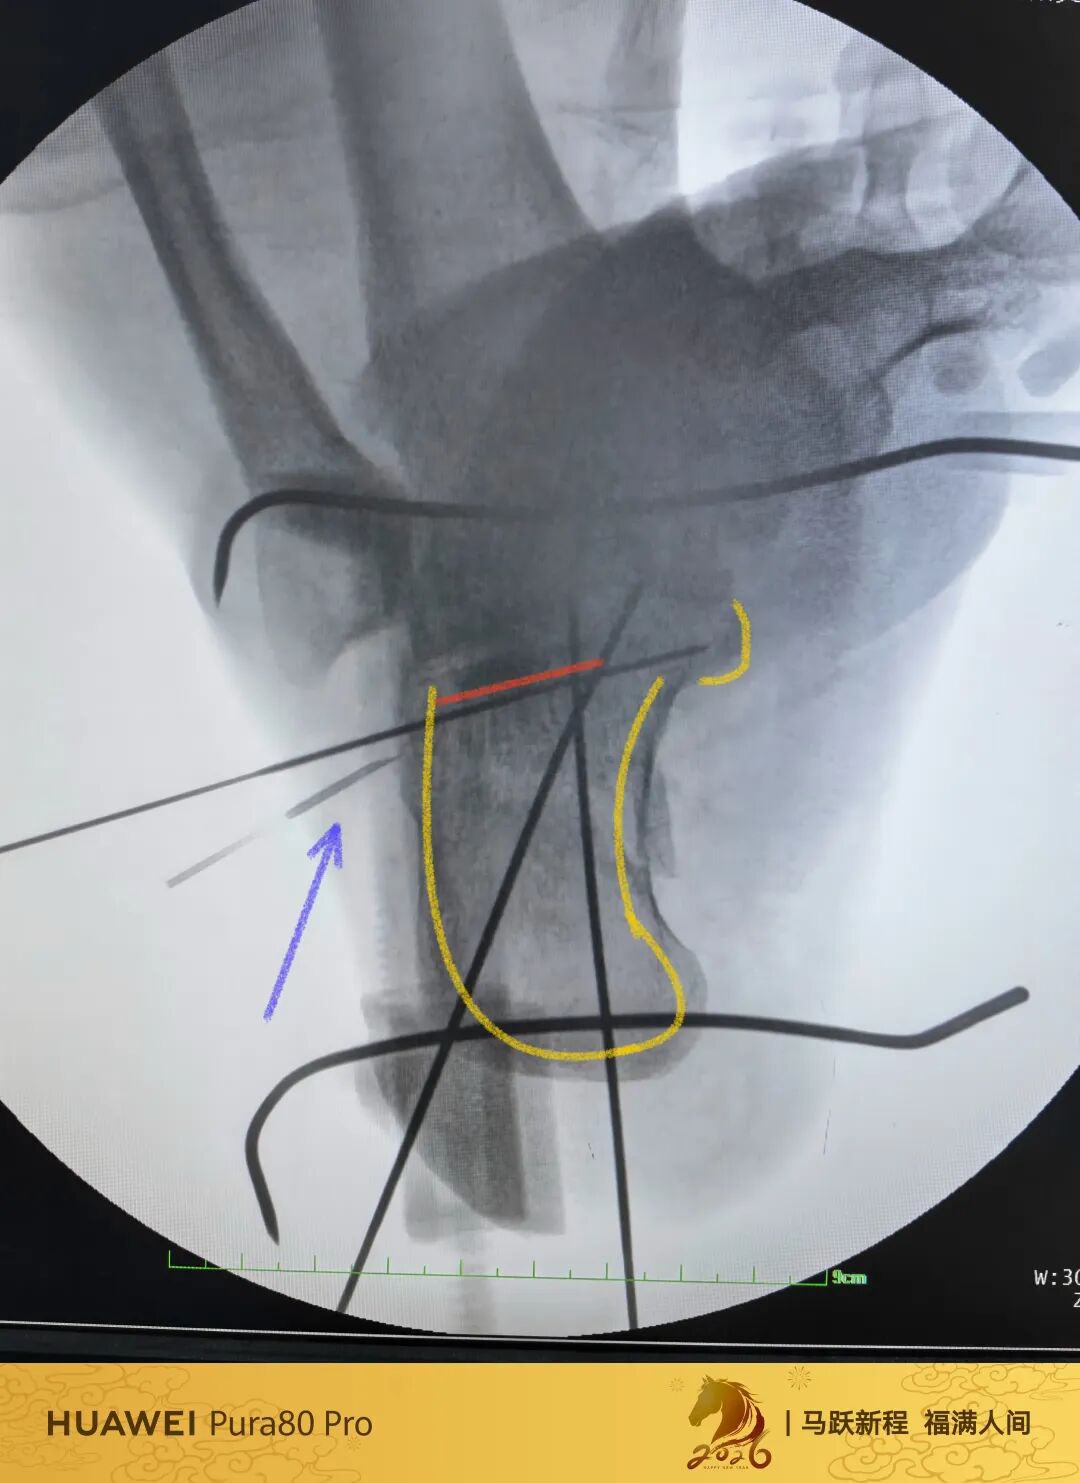

第60例跟骨微创了,虽然已经彻底放手,尽量只动嘴,但还是有小问题小瑕疵,无法完全避免。